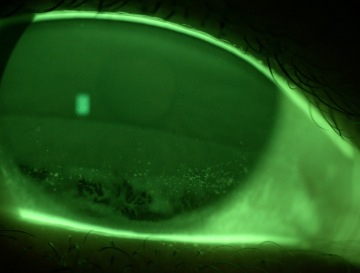

V rámci vyšetření posuzujeme stabilitu slzného filmu, stav víček a celkovou funkci předního segmentu oka.

Každý krok ošetření dokumentujeme pomocí fotografií. Díky tomu mají pacienti jasnou vizuální představu o tom, co se v předním segmentu oka děje a proč je zvolen konkrétní terapeutický postup.

Při vyšetření využíváme moderní přístrojovou techniku, která umožňuje přesnou diagnostiku a dokumentaci stavu oka.

Mezi používané přístroje patří: autorefraktometr, tonometr, štěrbinová lampa s fotoaparátem, keratograf a speciální čočky pro vyšetření očního pozadí bez nutnosti rozkapání očí.